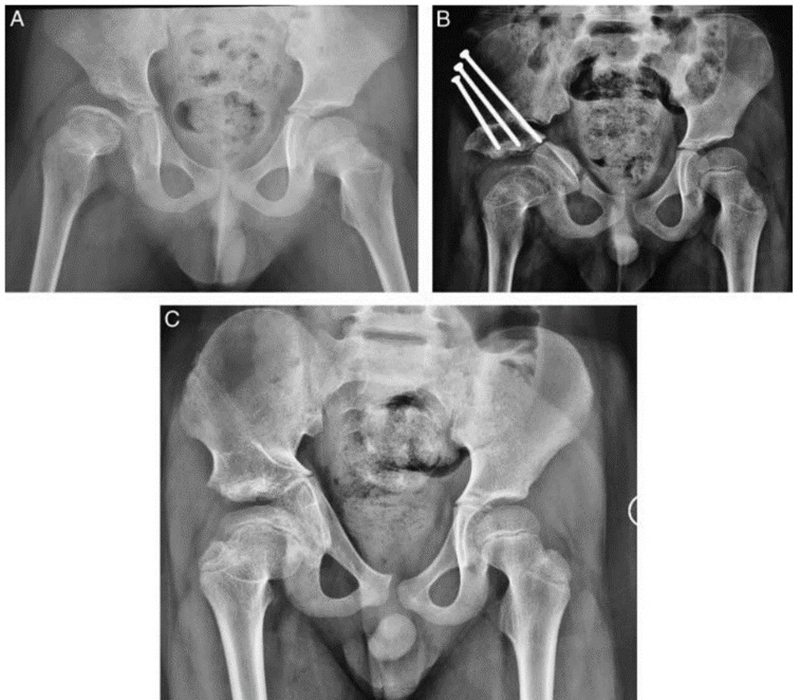

8岁患儿,双侧DDH,外院行切开复位手术后,残留畸形,经JST微创骨盆三联截骨后,末次随访提示髋关节包容好